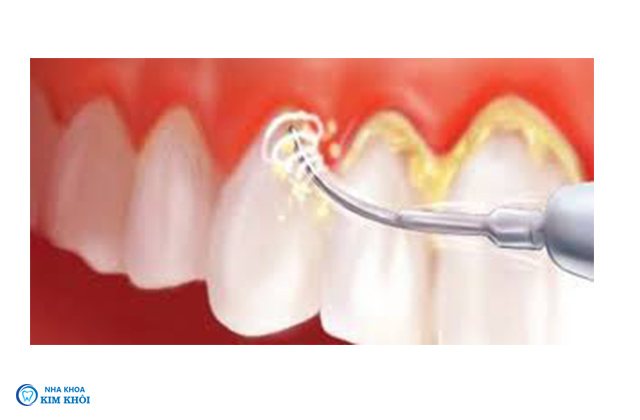

Trước đây bác sĩ nha khoa thường lấy cao răng bằng bộ dụng cụ cầm tay hoặc máy thổi cát để loại bỏ vôi răng. Hiện nay dụng cụ cạo vôi răng bằng song siêu âm được ưa chuộng hơn. Kỹ thuật hiện đại giúp giảm thiểu tối đa ê buốt rút ngắn thời gian điều trị. Sóng siêu âm an toàn tuyệt đối với cơ thể loại bỏ hoàn toàn mảng bám mà không xâm lấn răng và nướu.

Dụng cụ lấy cao răng bằng sóng siêu âm. Cấu tạo máy gồm 2 đầu, một đầu là tay cầm đầu còn lại nhỏ như đầu tăm sắc bén có thể chuyển động linh hoạt tới các ngóc ngách. Hoạt động với tần suất 28-30 kHZ độ rung vừa đủ để các mảng bám tự vỡ ra không làm tổn thương đến nướu và xung quanh.